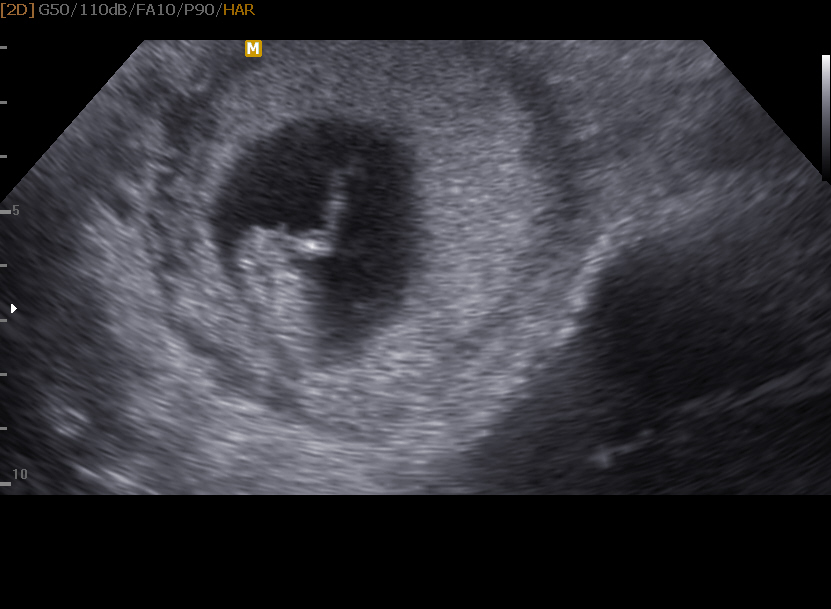

Attachment 17725Attachment 17726

I'm guessing boy from possibly what could be a penis in pic #1?

I had a very very similar scan pic as your first pic and he was a boy so I'm guessing boy! I kept hoping on his nub shot that it was part of the nub seen past the legs and when people guessed on mine they were hesitant as to whether it was part of the nub or not but I just knew in my heart it was. I'll try to find a link to it and post it so you can compare.